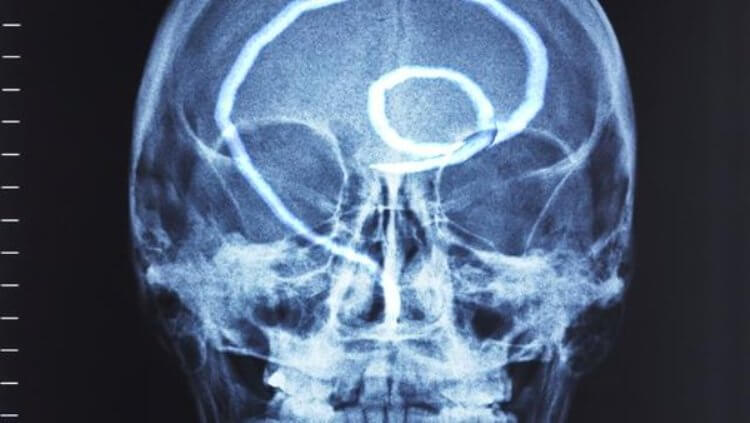

Još jedan čest slučaj je zaraza ljudskog mozga. Ovde dolazi do poremećaja funkcija, nervoze, umora, preterane razdražljivosti i iznenadnih promena raspoloženja. U kasnijoj fazi, kako se mozak puni parazitima, razvijaju se neke ozbiljnije bolesti i na kraju nastupa smrt.

"Imamo foto arhivu: fotografije snimljene za vreme autopsije kada smo otkrili različite parazite u ljudskim organima. Evo nekoliko primera. Upozoravam vas, užasni su".

Paraziti u ljudskom mozgu mogu da izazovu rak: